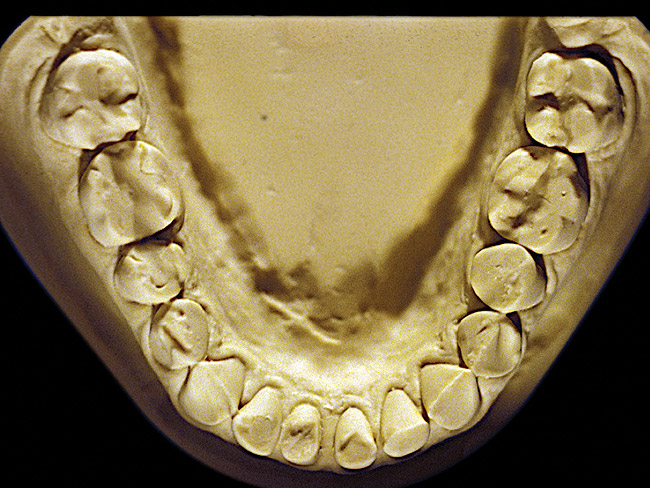

Figure 8  Moderate NCLTS from toothpaste, mandibular arch.

Figure 8

Figure 7 and Figure 8 are examples of NCLTS resulting from toothpaste. Upon examination, one could see that the overall anatomical detail of the teeth was faded with a sandblasted appearance. A closer view of the facial surfaces (Figure 9 and Figure 10) illustrates this to a greater degree and one can observe that the normal intricate facial anatomy was completely missing. It is interesting to note there was no cervical recession of the gingiva, even though every surface of every tooth had been abraded. This is due to the fact that this patient had always used a soft, round-ended filament toothbrush.21-22 This patient's sole desire regarding her oral hygiene was to get her teeth whiter.

So that the previous example is not misleading, the behavioral profile of the toothpaste abuser is not necessarily the "caries-free immaculate oral hygiene patient," but can be virtually anyone who brushes their teeth with toothpaste. Figure 11 and Figure 12 illustrate a more advanced example of toothpaste abuse showing a patient with multiple restorations and some unkempt teeth. The anatomical details were faded with a sandblasted appearance and the silver alloy restorations were highly polished. The facial surfaces of the mandibular canines and premolars were affected the most, creating the pathognomonic pattern. Figure 13 and Figure 14 are a close-up view of this area, illustrating a cupping or cratering effect, but of the asymmetrical variety. This patient did not like the color of his teeth and spent an inordinate amount of time brushing his teeth. Again, likewise due to the exclusive use of a round-ended, soft-bristle toothbrush, note there was no cervical gingival recession in this case either. When the featured casts illustrating toothpaste abuse (Figure 7, Figure 8, Figure 9, Figure 10, Figure 11, Figure 12, Figure 13 and Figure 14) were hand-articulated, the worn surfaces did not match up and the diagnosis of toothpaste abuse was confirmed.